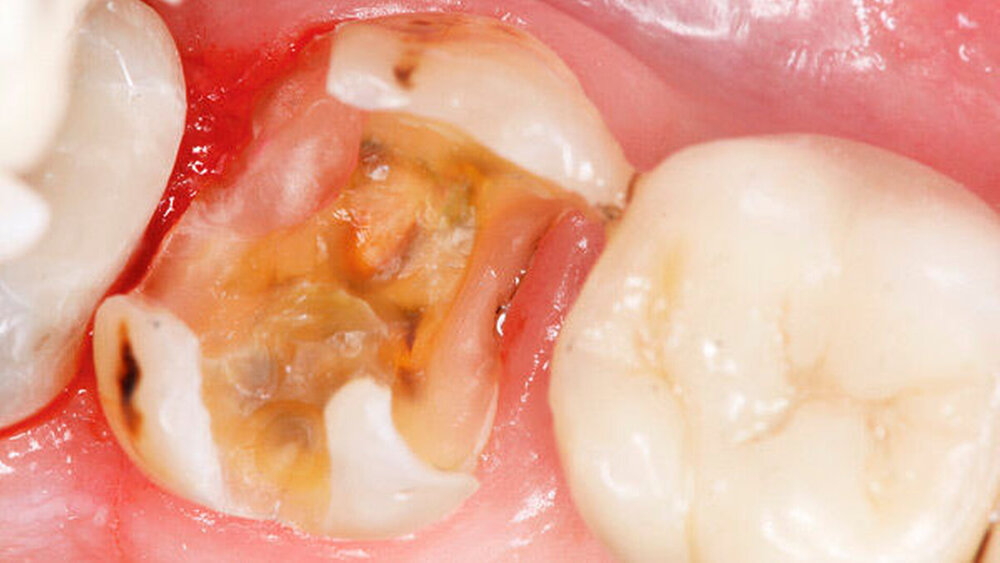

Dualhärtende Komposite kommen häufig beim Aufbau stark zerstörter Zähne vor der Versorgung mit indirekten Restaurationen zum Einsatz. Eine weitere Indikation für dualhärtende Komposite ist die Befestigung von indirekten Restaurationen oder Wurzelkanalstiften, wo das Komposit oft nicht ausreichend lichtpolymerisiert werden kann. Seltener werden für diese Anwendungen ausschließlich selbsthärtende Komposite verwendet.

Das Prinzip der Selbstkonditionierung ist für Aufbaurestaurationen aus mehreren Gründen vorteilhaft. Zum einen liegt, wenn ein Stumpfaufbau erforderlich ist, meist ein ausgedehnter Defekt mit einer entsprechend großen Dentinwunde vor. Die Selbstkonditionierung ist hier schonender für das Pulpa-Dentin-System als die aggressivere Ätzung mit Phosphorsäure. Ein weiterer Vorteil ist die größere Beständigkeit des Dentinverbunds bei Verwendung geeigneter SE-Systeme im Vergleich zu Etch-and-Rinse (ER)-Systemen. Hinzu kommt ein rein praktischer Aspekt. Der Verzicht auf die Phosphorsäure(PS)-Ätzung mit dem erforderlichen Abspülen des Ätzgels kann in schwierigen Situationen „spielentscheidend“ sein. Wenn – wie bei Universaladhäsiven – noch auf einen weiteren Arbeitsschritt verzichtet werden kann, ist das besonders vorteilhaft.

Auch in folgender Situation kann die Verwendung eines Universaladhäsivs zur Verankerung der Aufbaufüllung von Vorteil sein: Häufig verlaufen die Kavitätenränder nach der Kariesexkavation iso- oder subgingival, was den Einsatz von Adstringenzien zur Blutstillung erforderlich machen kann. Eine Kontamination des Dentins mit adstringierenden Materialien führt zu signifikant verschlechterten Haftwerten [Ajami et al., 2013; Chaiyabutr und Kois, 2011; Harnirattisai et al., 2009; Kuphasuk et al., 2007; Mohammadi et al., 2012]. Eine Phosphorsäure-Ätzung nach Abspülen des Adstringens kann die Haftung positiv beeinflussen [Appelt et al., 2013].